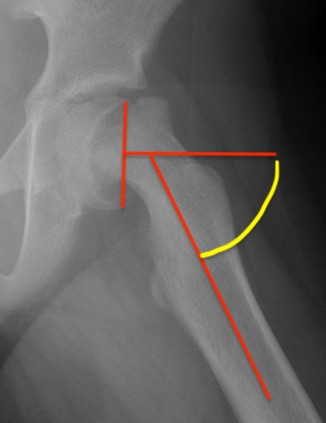

Southwick classification

Southwick Angle / Slip Angle

- epiphyseal-diaphyseal angle on frog leg lateral

- mild <30°

- moderate 30- 50°

- severe >50°

Mild Moderate Severe